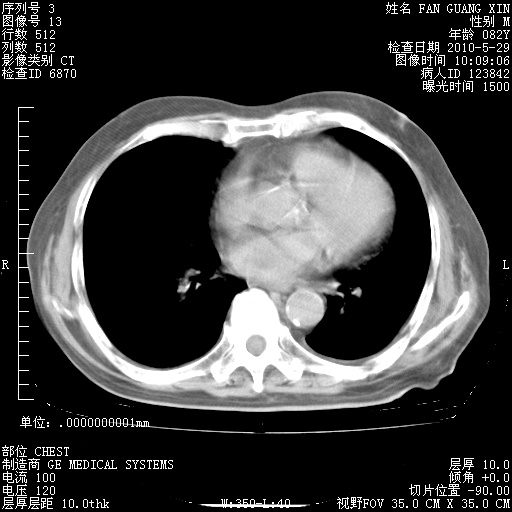

再治疗10天后的肺部CT

阅读此次胸部CT,肺间质渗出性改变较入院时有吸收。目前从体温、白细胞、中性分叶明显增高,肯定存在细菌感染(发生医院感染哦,若无消化道及泌尿系统等感染的依据,肺部感染可能大)。若你院头孢哌酮舒巴坦钠耐药率较高,同意你的方案,若48小时体温仍高,可考虑使用碳青霉稀类抗菌药物,同时可予超声雾化、注意滴数时加大液体量。白蛋白33.30g/L较低哦,需加强营养等支持治疗。